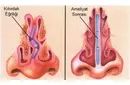

Diz Kıkırdak Belirtileri ve Tedavisi Diz kıkırdağı, diz ekleminin düzgün çalışabilmesi için kritik bir yapı oluşturur. Kıkırdak, eklem yüzeylerini kaplayarak sürtünmeyi azaltır ve hareket sırasında şok emici bir görev üstlenir. Ancak, çeşitli nedenlerden dolayı diz kıkırdağında hasar meydana gelebilir. Bu yazıda, diz kıkırdağında oluşabilecek belirtiler, bu belirtilerin nedenleri ve tedavi yöntemleri detaylı bir şekilde ele alınacaktır. Diz Kıkırdak Hasarının Belirtileri Diz kıkırdağında meydana gelen hasar, çeşitli belirtilerle kendini gösterebilir. Bu belirtiler, hasarın ciddiyetine ve nedenine bağlı olarak değişiklik gösterebilir. Yaygın belirtiler şunlardır:

Diz Kıkırdak Hasarının Tanısı Diz kıkırdak hasarının tanısı, genellikle bir ortopedi uzmanı tarafından konulur. Tanı sürecinde şu yöntemler kullanılabilir:

Diz Kıkırdak Hasarının Tedavi Yöntemleri Diz kıkırdak hasarının tedavisi, hasarın ciddiyetine ve bireyin genel sağlık durumuna bağlı olarak değişir. Tedavi yöntemleri arasında şunlar bulunmaktadır: